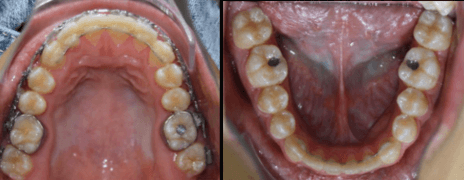

Fotografías Intraorales Pre Quirúrgicas

El paciente se ha tratado bajo el concepto de Surgery First ya que se realizó la intervención quirúrgica de forma temprana con una mínima alineación y nivelación, evitando las desventajas de una larga etapa de ortodoncia prequirúrgica.

Fase Ortodoncia Post Quirúrgica y Finalización

• Realineación y nivelación

• Consecucion de las Clase I molares y caninas

• Correcta ubicación de los dientes en sus bases oseas

• Torques y tips correctos

• Logro del correcto Overjet y overbite

En esta fase de Ortodoncia post quirúrgica donde se aprovecho el fenómeno de Aceleración Regional que se activa gracias a la cirugía ortognática y se lograron los objetivos oclusales, funcionales y estéticas en poco tiempo.